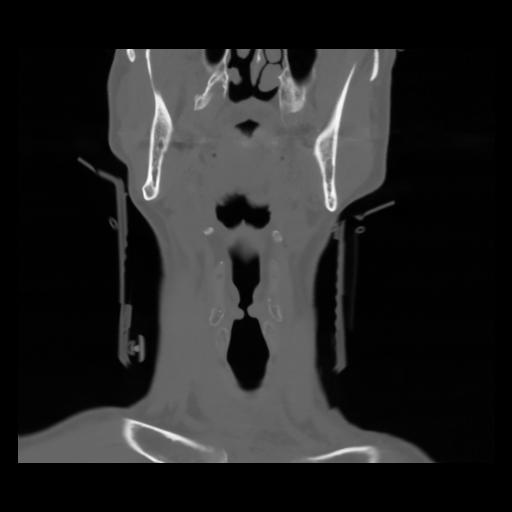

13 P.BLANDAS,,Coronal,2.000,P.BLANDAS,Coronal,